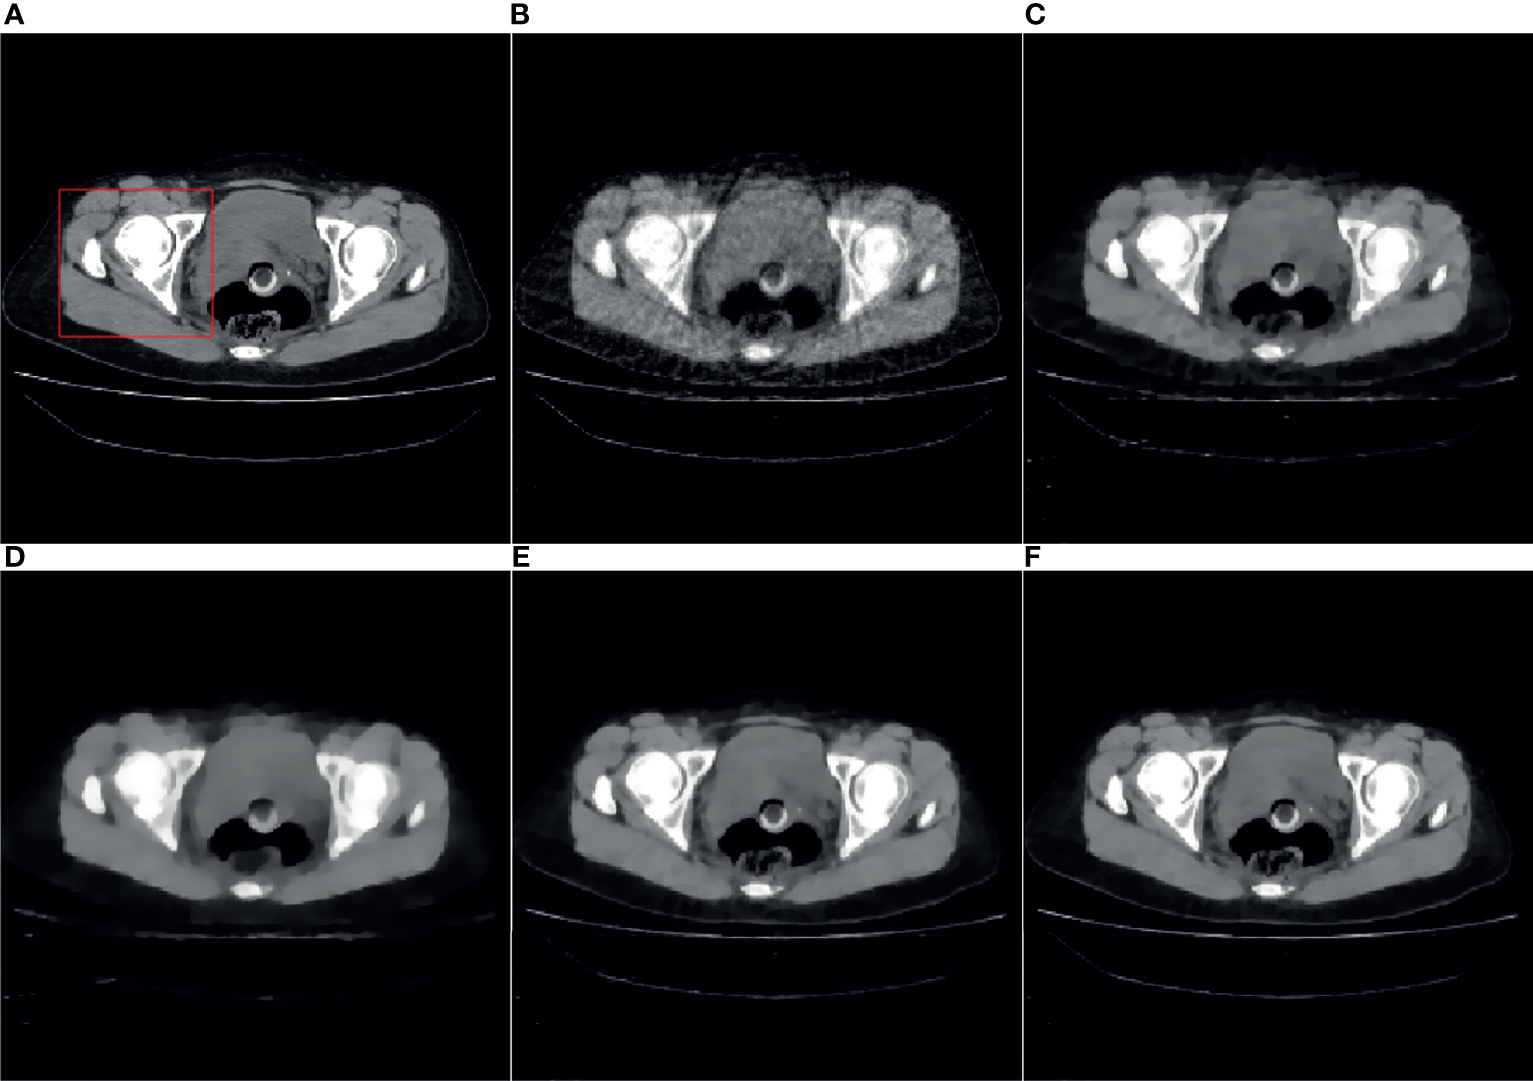

4.3 Actual Data Reconstruction

Figures 4, 5 are the reconstruction results of CBCT of the place that close to the center plane and bottom plane, respectively, it can be seen from Figure 4B that with the sparse angle projection, the reconstruction result of SART near the center plane still has serious artifacts. The reconstruction result of the SART-TV algorithm has a significant blocky effect, and many details are blurred. The reconstruction result of ASD-POCS algorithm is better than that of SART-TV reconstruction, but compared with the TpV minimization algorithm, the blocking effect is still more serious. The reconstruction result of the TpV-GIF algorithm not only suppresses artifacts as effectively as TpV, but also has better detail restoration, which can be seen in Figure 6.

Figure 4 40th slice reconstruction result: (A) reference image; (B) SART; (C) ASD-POCS; (D) SART-TV; (E) TpV; (F) TpV-GIF.

Figure 5 260th slice reconstruction result: (A) reference image; (B) SART; (C) ASD-POCS; (D) SART-TV; (E) TpV; (F) TpV-GIF.

Figure 6 ROI area enlarged image: the first row and the second row are the enlarged images of the red box area in Figure 4 and Figure 5, from left to right there are the reference image, SART, ASD-POCS, TpV and TpV- Reconstructed image of GIF. The (A–E) in this figure are correspond to the (A–E) in Figure 4 and Figure 5.

Observe the details indicated by the black and white arrows in Figure 6, and compared with the reference image, you can see that the ASD-POCS reconstruction result is relatively fuzzy, and details of the SART reconstruction image are more complete, but they all have serious artifacts. The details of the TpV reconstruction image are better preserved while the performance of TpV-GIF is even better. For the area indicated by the red arrow, the SART does not perform well in suppressing artifacts, the ASD-POCS blurs the details and has a blocky effect, on the contrary, TpV and TpV-GIF reconstruction results are better, the artifacts are suppressed while the edges are preserved.